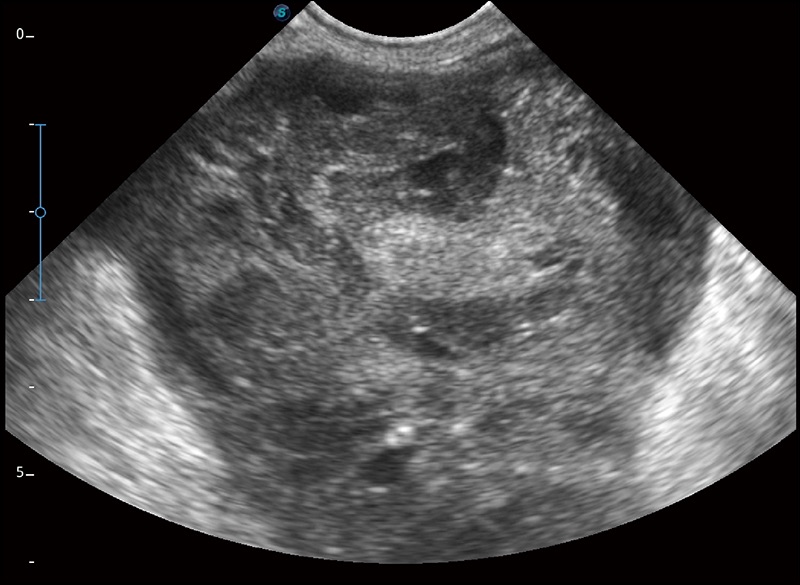

空间复合成像

优化不同角度的图像